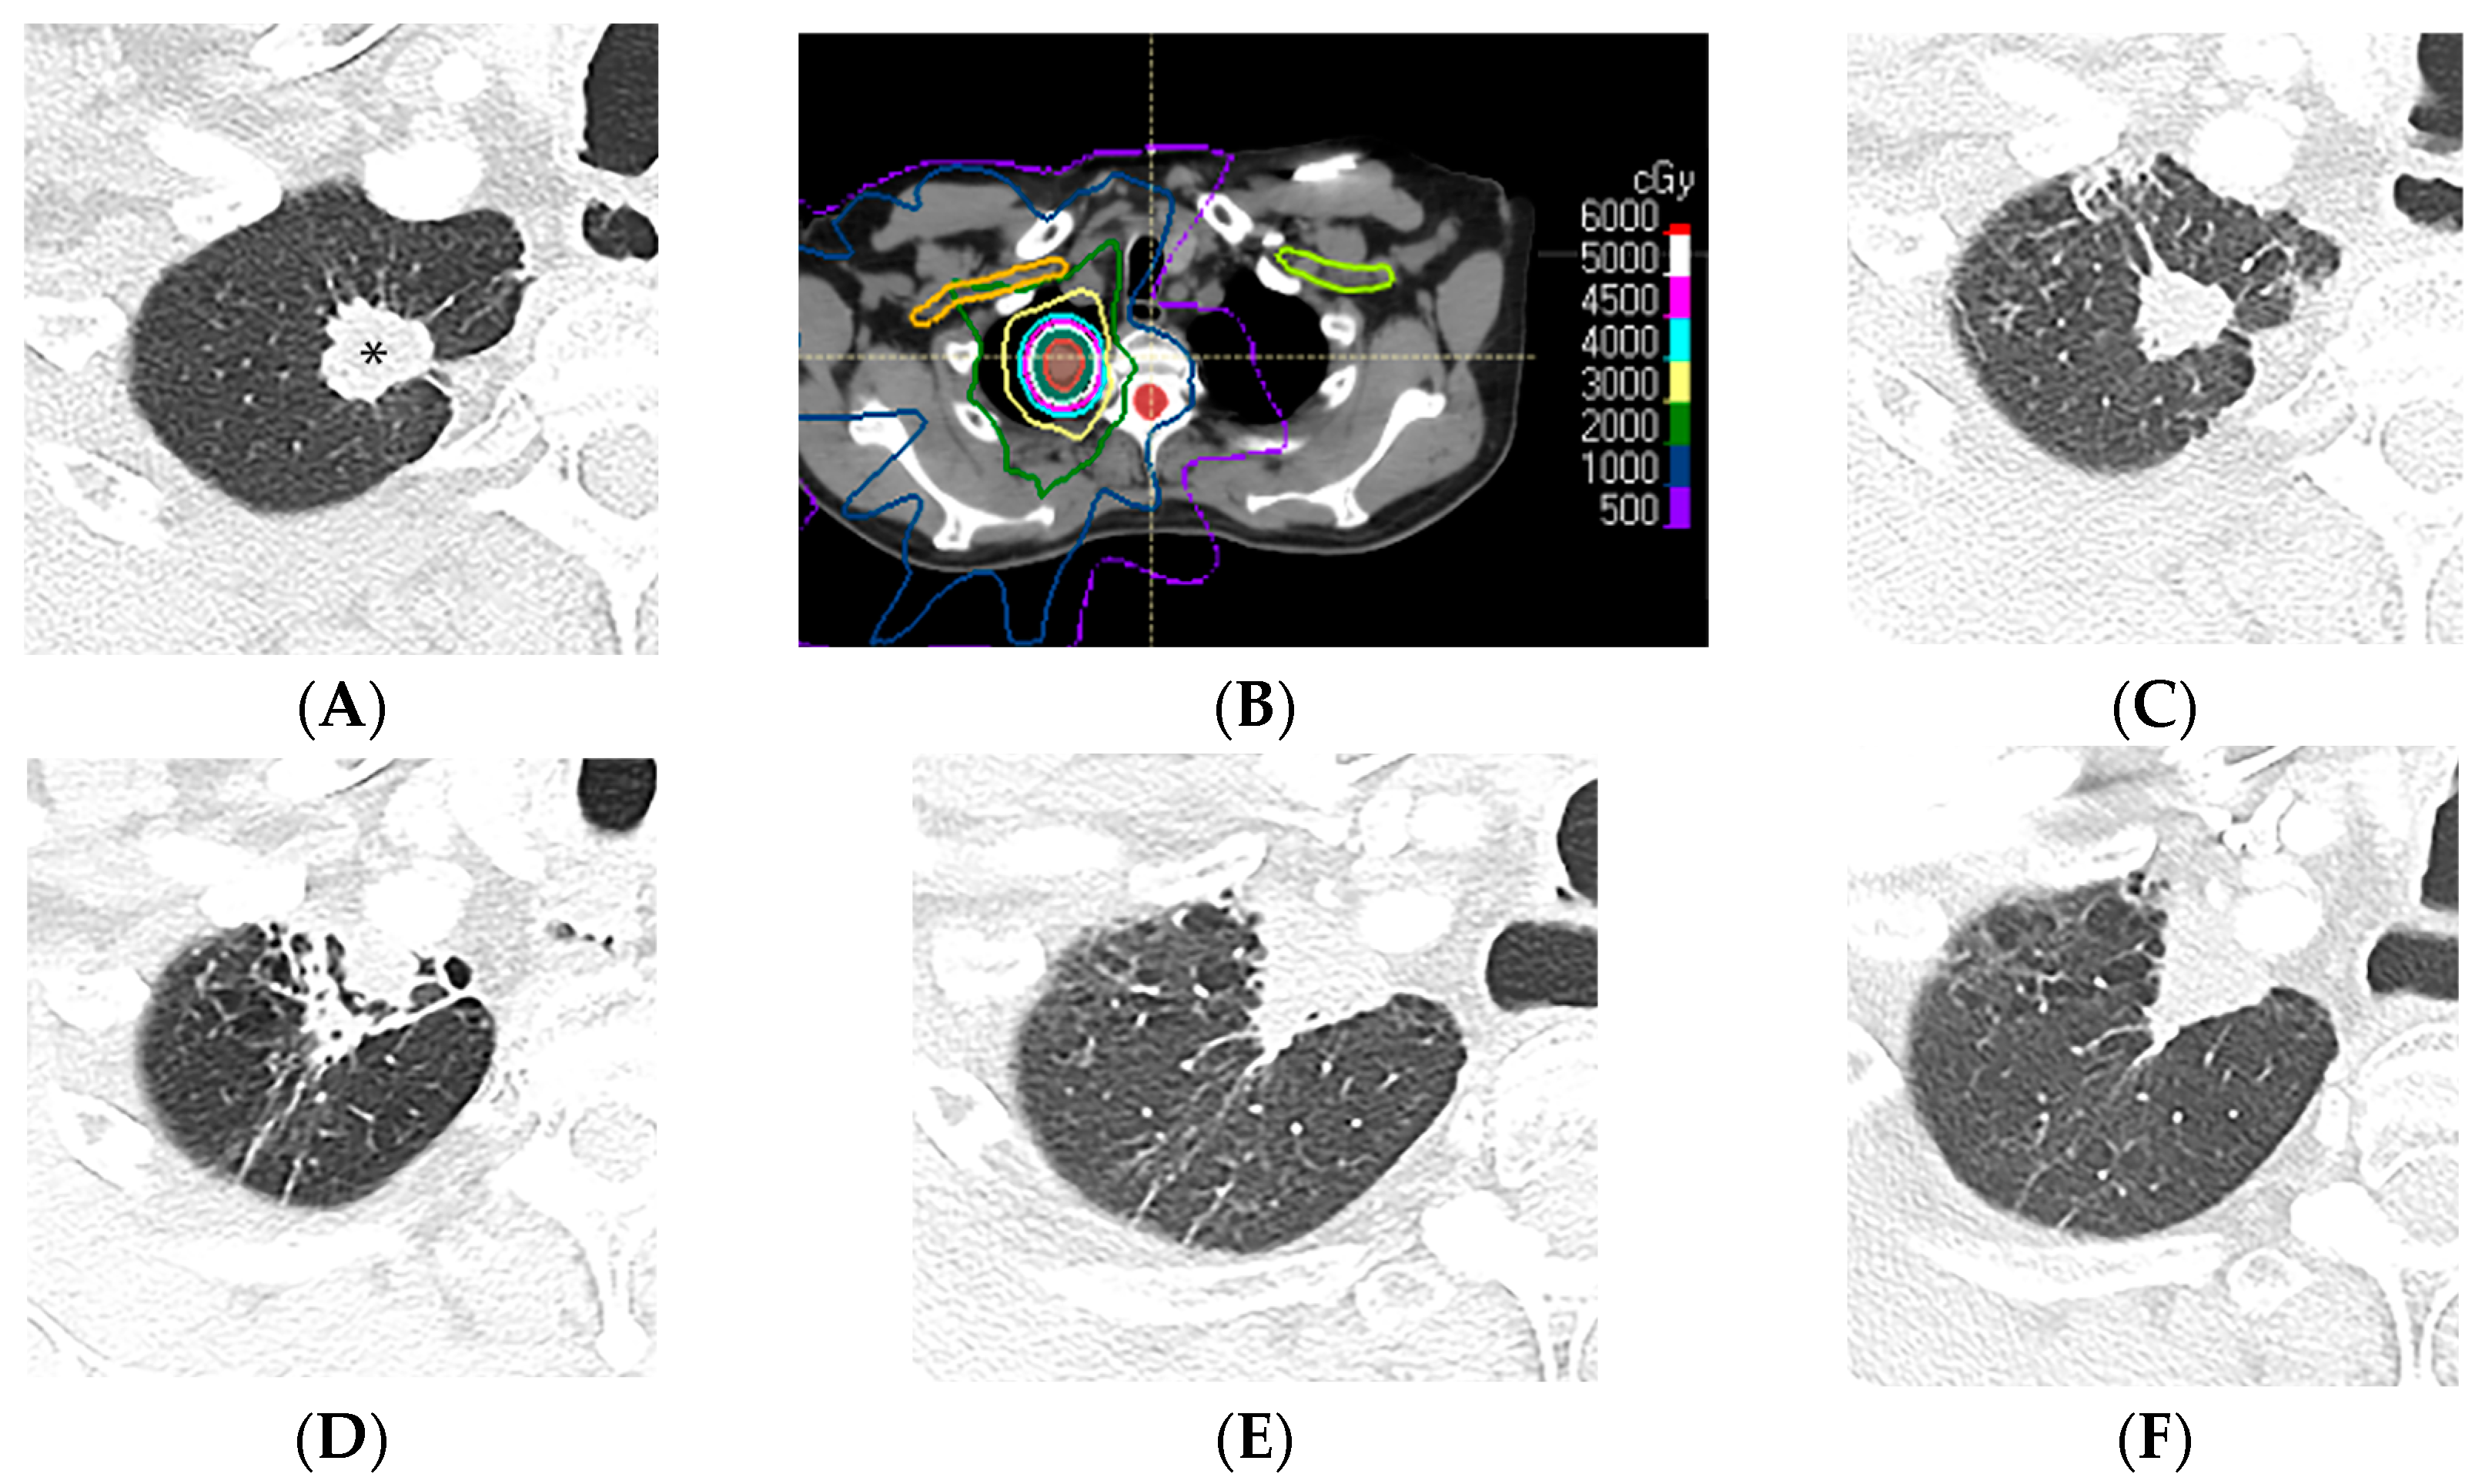

2.4. Stereotactic Body Radiotherapy

3. Post-Radiation Changes

4. Specific Imaging Patterns in RILI